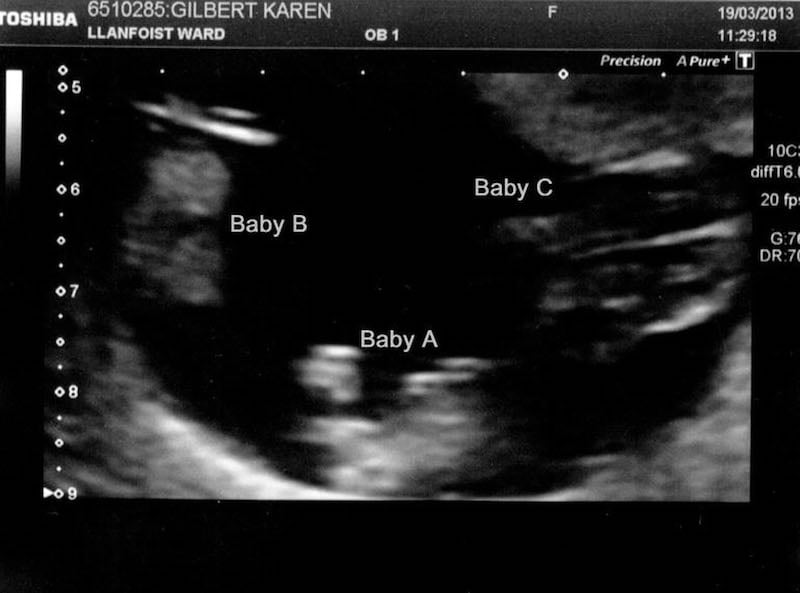

Karen and Ian Gilbert were still newlyweds when they found out Karen was pregnant. Karen initially thought she was expecting one baby, but when she started to experience severe pain in her abdomen, she feared a miscarriage. As it turned out, Karen was wrong on both counts. She was actually pregnant with triplets, and the babies were fighting for space inside her belly! Incredibly, the Gilbert triplets were conceived naturally from one egg, which is extremely rare.

Karen Gilbert was shocked when an ultrasound revealed she was pregnant with triplets. They were conceived naturally from one egg, beating a 200 million-to-one chance.